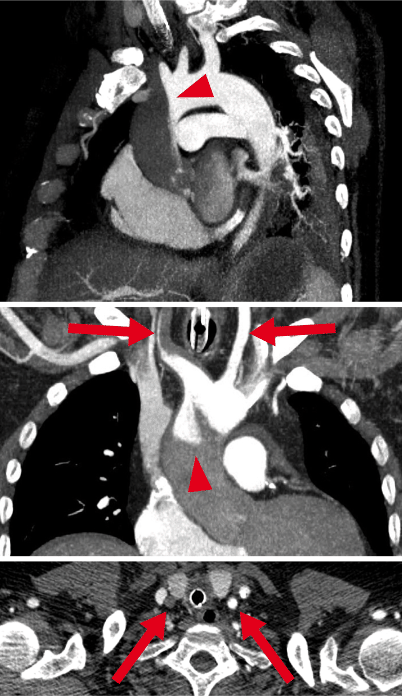

The retrograde ECMO output meets the antegrade LV output at a zone called the “watershed” [36, 45, 46]. In most cases the watershed occurs somewhere between the aortic root and the diaphragm (Fig. 2), depending on the native output of the heart: The higher the LV output relative to ECMO output, the more distal the watershed [46]. Since the output of most ECMO devices is nonpulsatile, pulse pressure measured at the right radial artery serves as an estimate of LV output [46]. For example, a blood pressure of 80/70 mm Hg at an ECMO flow of 4.5 l/min suggests a watershed in the aortic root, whereas a blood pressure of 140/70 mm Hg at the same ECMO flow suggests a watershed in the descending thoracic aorta. Blood from the ECMO is usually well oxygenated; however, oxygenation of blood from the LV depends on the respiratory function of the lung. Therefore the position of the watershed is critical for oxygenation. Aortic root oxygenation cannot be continuously measured with standard equipment. If the watershed is located in the ascending aorta and blood from the LV has an oxygen saturation of, e. g., 56% during lung failure, then the heart itself may be perfused for hours or days with an extremely insufficient oxygen saturation from the lungs in the presence of sufficient oxygenation of all other organs from the ECMO. In this context, the extreme form of dismal circulation is the “two-circulation-syndrome” [47]: If the venous cannula is incorrectly placed in the inferior caval vein, so that only blood from the lower body is drained, blood from the upper body goes through the lungs to the ascending aorta. Then venous drainage from and the perfusion of the upper body are both disconnected from that of the lower body. This results in a “Harlequin”-like appearance of the patient, with upper-body hypoxia and lower-body hyperoxia.

Fig. 2

Watershed phenomenon during VA-ECMO. Computed tomography. Antegrade blood flow (low contrast) from the heart competes with retrograde blood flow (high contrast) from the ECMO in the aorta, resulting in a watershed phenomenon (arrowhead). Here computed tomography of a patient with pulmonary embolism and reduced cardiac output demonstrates a rather proximal watershed, leading to perfusion of the right carotid artery with “heart blood” (dark) and the left carotid artery with “ECMO blood” (bright, arrows). Upper panel: sagittal oblique maximum intensity projection (MIP); middle panel: coronal oblique MIP; lower panel: transverse plane. (From Napp et al. [36]; © L. C. Napp, C. Kühn, M. M. Hoeper et al. 2015. This publication is an open access publication, available on springerlink.com)